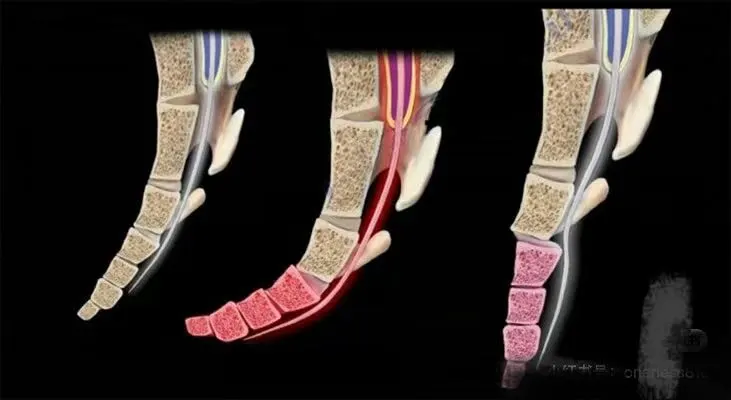

最近遇到几个个案 骨盆后倾下掉 再摸尾椎基本上都是勾进去的 其实尾椎尖下面是尾闾穴 尾闾穴是我们人体的生发之地 尾椎尖慢慢松开 骨盆会慢慢上提 而且上臀会饱满 并且股骨头的角度也会变化 最有意思的事 尾椎尖松开 肛门的紧张会释放 会不断排气以及开始排宿便 尾椎一调 身体重心会向后 原来站着总是不自觉向前顶胯骨盆前移 自然消失 而且坐着很容易坐在坐骨上 如果你练瑜伽 骨盆无论怎样练习 都很难翻上来 你一定摸摸自己的尾椎是否勾进去的 也可以拍骶尾椎侧位片发到评论区里